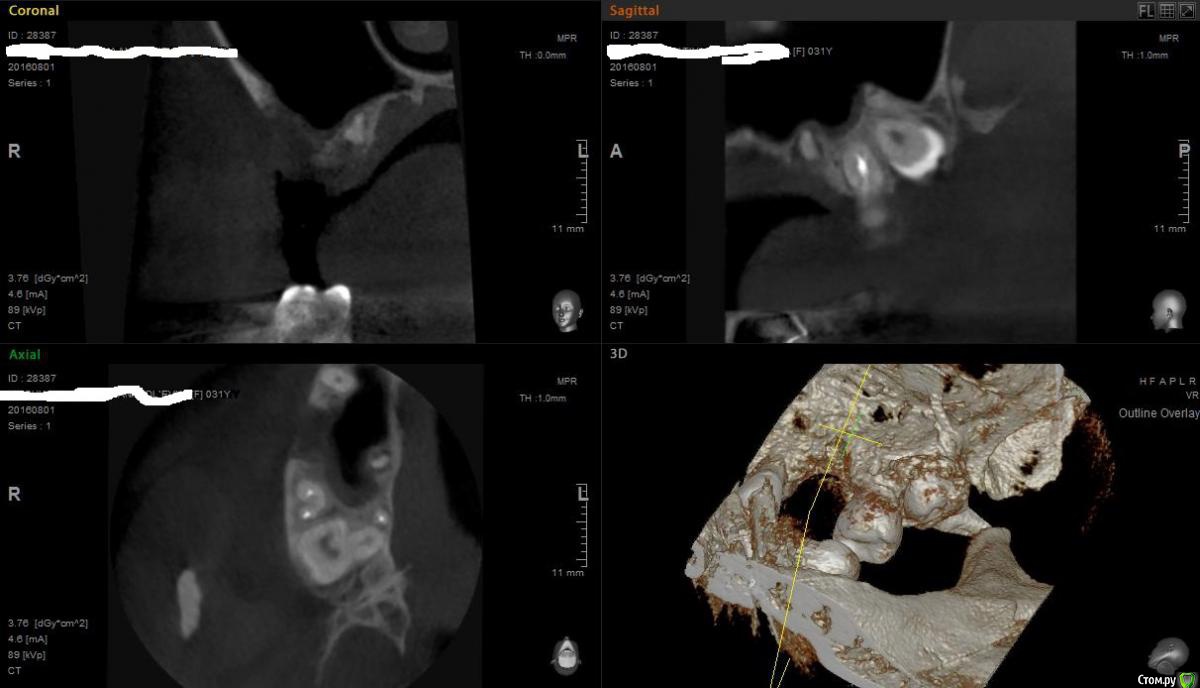

Павел7809 Опубликовано 3 августа, 2016 Поделиться Опубликовано 3 августа, 2016 Собственно все достаточно просто, пациент на синус, Зуб удалял я сам, каких то проблем насколько я помню небылоСделал на всякий случай кт шку, бегло ее посмотрел, записал на операцию. Заказал материалы!!! И тут сижу ее, прикидываю имплант - и что я вижу - корень! Как я мог проморгать(или может это и не корень а какой нибудь осколок? Прошу совета подальнейшей тактике. Возможно ли совместить открытый синус с удалением этого корешка? Или нежелательно? Ссылка на комментарий

Fibez Опубликовано 3 августа, 2016 Поделиться Опубликовано 3 августа, 2016 Это не осколок, это верхушка небного корня. Делать то, что запланировали. Плюс корень удалить. И после окончания операции вскользь сказать пациенту, мол еще какой-то мелкий фрагмент корня удалил "за компанию". 2 Ссылка на комментарий

Павел7809 Опубликовано 3 августа, 2016 Автор Поделиться Опубликовано 3 августа, 2016 Это не осколок, это верхушка небного корня. Делать то, что запланировали. Плюс корень удалить. И после окончания операции вскользь сказать пациенту, мол еще какой-то мелкий фрагмент корня удалил "за компанию".А возможно инфицирование графта в синусе от этого "хвоста", и не лучше ли было бы сначала удалить, через месяцок синус делать? Ссылка на комментарий

Fibez Опубликовано 3 августа, 2016 Поделиться Опубликовано 3 августа, 2016 возможно. не лучше. Ссылка на комментарий

Аслан Опубликовано 3 августа, 2016 Поделиться Опубликовано 3 августа, 2016 Имхо удалить вместе с синусом и засыпать графтом. 1 Ссылка на комментарий

voff Опубликовано 4 августа, 2016 Поделиться Опубликовано 4 августа, 2016 КаТэ полезная вещь Убрать и засыпать. Имплант "прикидывать" ни к чему и не к чему вообще тут... Ссылка на комментарий